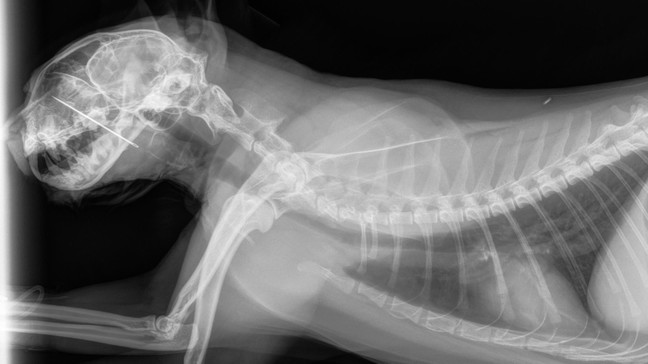

Portland vet saves Kevin, curious cat who ate sewing needle, impaled nasal cavity

PORTLAND, Ore. — A Portland cat named Kevin let his curiosity get the better of him when he ate a sewing needle, which then impaled into his nasal cavity - but luckily, a vet team was able to save the day!

Kevin decided to try a little taste of the sewing needle.... which became lodged in his mouth, impaling through his hard palate and into his nasal cavity.

At DoveLewis, it was decided that Kevin needed a sedated oral exam to find the cause of the problem. That’s when the team discovered the sewing needle embedded in Kevin’s mouth, with the blunt end pressing against the base of his tongue.

Thankfully, the team was able to quickly and gently remove the needle, ensuring minimal risk of further injury.

Remarkably, the needle was extracted whole, without breaking or causing additional harm.